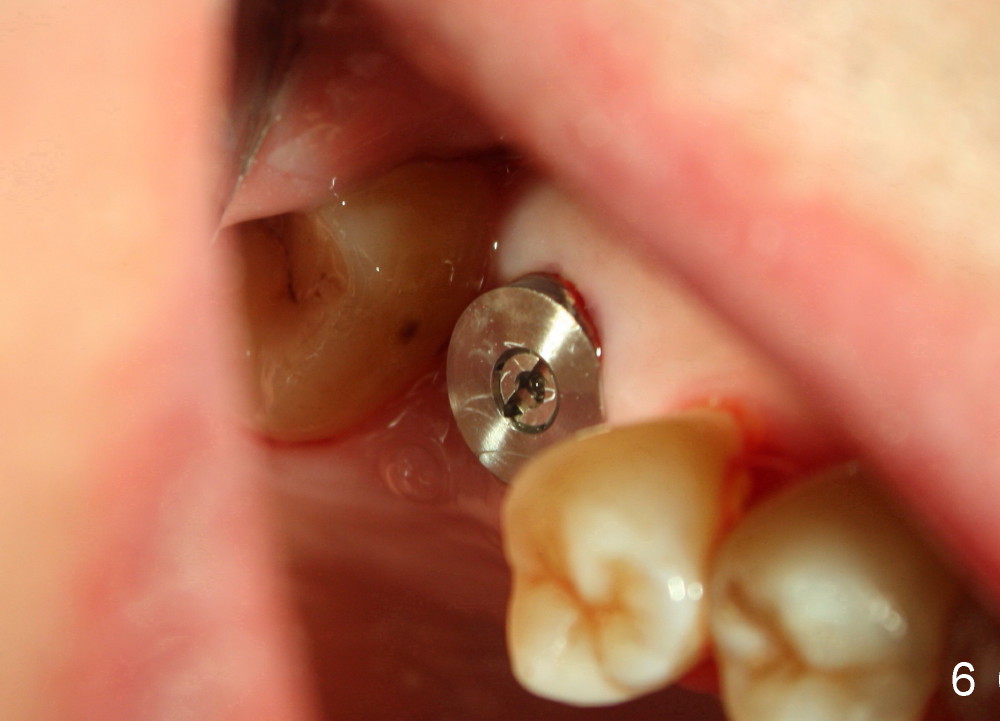

Our experience demonstrates higher failure rate associated with shorter implant in this situation. The depth of the osteotomy is then increased to 14 mm using the same series of osteotomes and taps. The bone at the top of the osteotomy finally wears off when the last tap is applied (7x17 mm). But the sinus membrane is intact. Osteogen is pushed into the osteotomy before placing a 7x14 mm implant with insertion torque > 60 Ncm (Fig.5). The implant contacts the gingiva tightly; no suture is necessary. There is no intra- or postop nasal hemorrhage. The wound heals 8 days postop (Fig.6). There is bone surrounding the apical portion of the implant in the sinus (Fig.7,8 *) 3.5 months postop. The implant is stable. There appears no crestal bone resorption 7.5 months post cementation (Fig.9 ^). Sinus lift is visible 16 months post cementation (Fig.10 (trimmed panoramic X-ray) arrowheads). There is discomfort between #2 and 3, probably due to poor oral hygiene. There is no deep pocket or bone loss (Fig.11, 26 months post cementation).